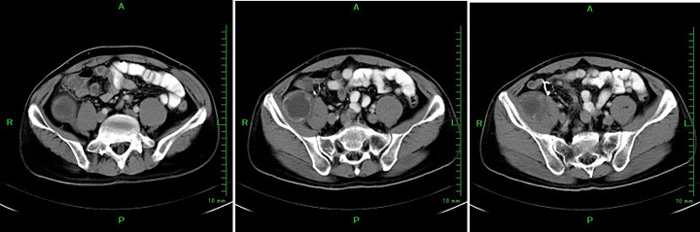

MixiMRI勉強会 脂肪抑制いろいろ 最近やっと勉強する気になったのですが、疑問が次から次へと出てきます。ここでは脂肪抑制についてお聞きしたいと思います。 脂肪抑制にもいろいろありますよね。 T2、PD、T1など。また、SE系、GRE系の違いもありま. ・骨盤部ではmriを,腹部ではctを第一選択にする. ・t1強調画像ではt1が長いほど磁化の回復が遅れるため信号が低く(黒く),t2強調画像ではt2 が長いほど磁化の減衰が遅れるため信号が高く(白く)描出される.t1とt2の組み合わせで組 t1強調画像はctの画像と似ており、脳の解剖学的な構造が見やすいという特徴があります。. 造影剤投与によりT1緩和時間が大きく短縮されますので基本的に脂肪抑制T1強調画像をベースに撮影が行われます。 ③実際の症例を提示します。 1) Stage I 腎細胞癌のdynamic MRI画像です。 左腎臓上極に1cm大の遷延性濃染する腫瘍を認めます。.

腹部影像 肾淋巴瘤 的临床表现 Mri特点及鉴别诊断 建议收藏 看点快报